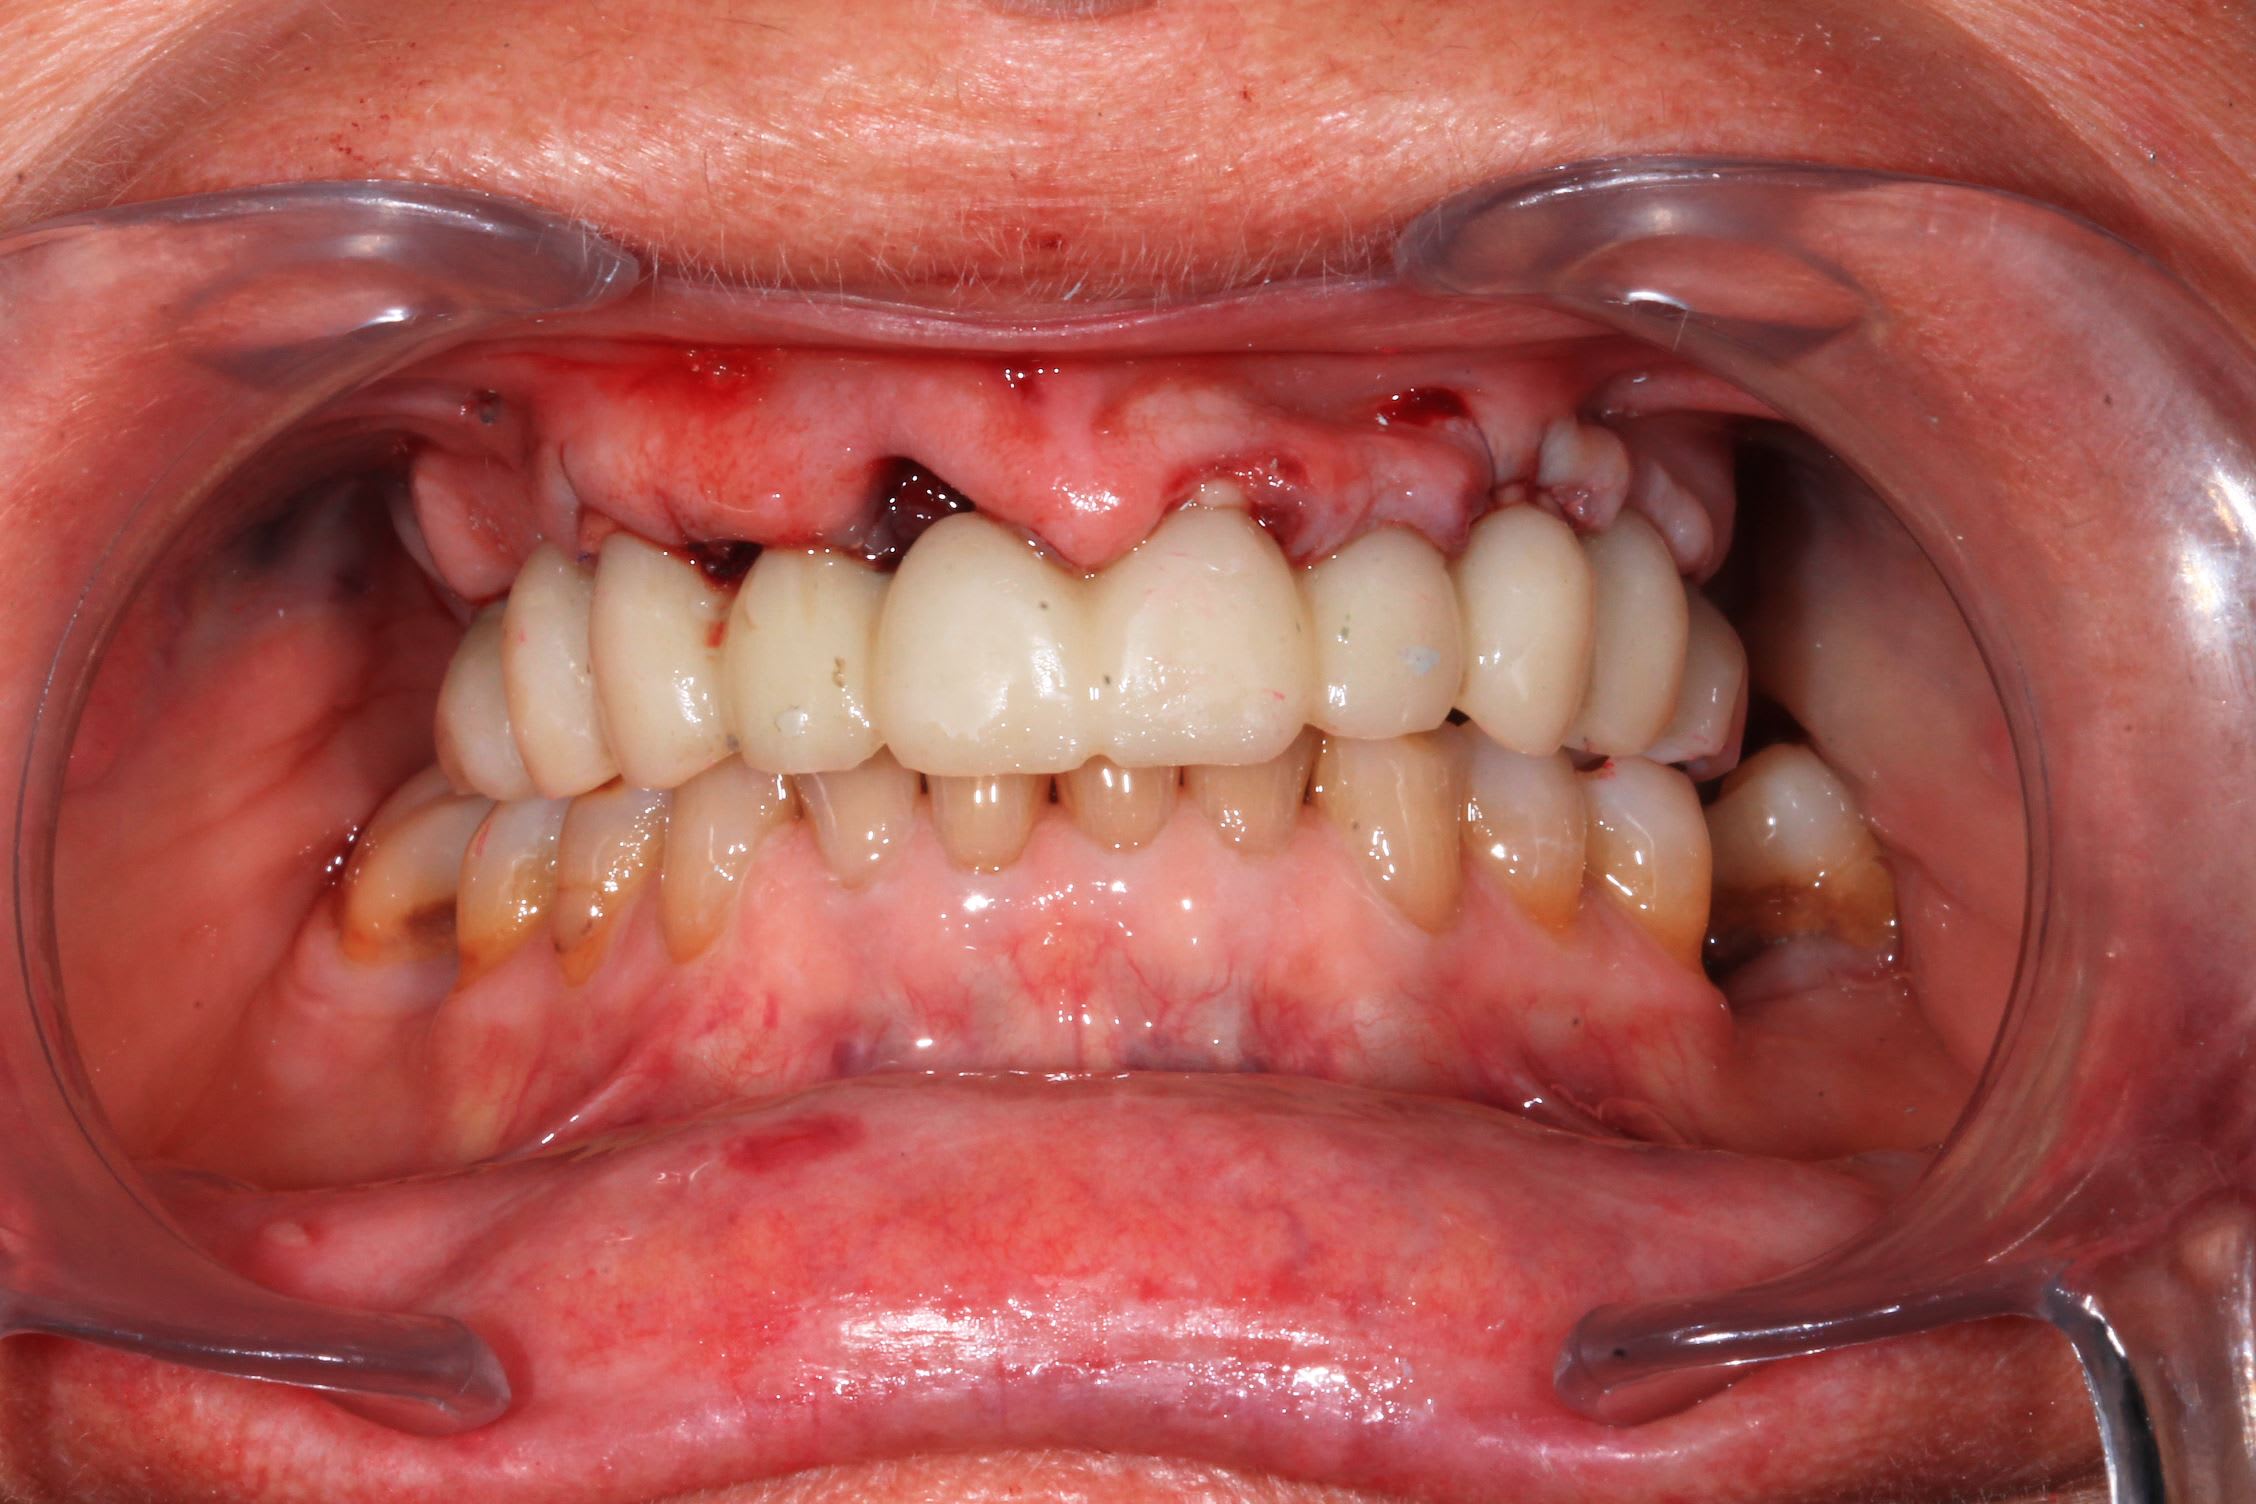

Le cas de la semaine derniere : implants super stable. Premier coup de bistouri a 9h45, patiente sortie à 13h. J'ai galéré avec un satané apex cassé et des canines rebelles : presque 3/4 h pour les extractions !